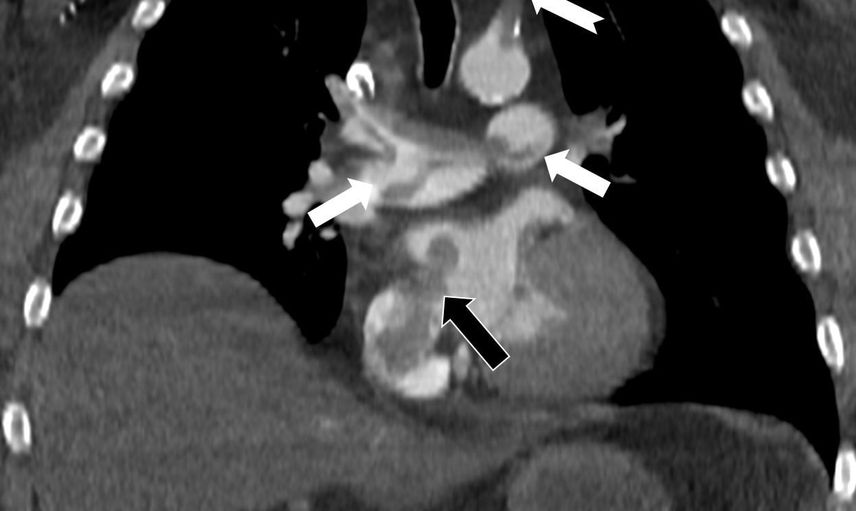

Özel Denizli Tekden Hastanesi'nde önemli çalışmalara imza atan Radyoloji Uzmanı Prof. Dr. Nevzat Karabulut, kalpteki gizli deliklerin hayatı tehdit eden paradoks emboliye neden olabileceğini ortaya koydu.

Kalp ve akciğer görüntülemesi konusundaki uluslararası bilimsel çalışmaları ile dikkat çeken Prof. Dr. Karabulut, Radiology dergisinin 2025 Kasım sayısında "Paradoxical Embolism with Clot-in-Transit in Atrial Septal Defect" başlıklı çalışmasını yayımladı. Bu çalışmada, penis ameliyatı sonrası ani göğüs ağrısı, nefes darlığı ve kol uyuşması şikayetiyle hastaneye başvuran 60 yaşındaki bir bireyde tespit edilen daha önce fark edilmemiş kalp odacıkları arasındaki delikten geçen pıhtının ciddi bir risk taşıdığına dikkat çekildi.

Pıhtı Riskleri ve Gözlemler

Prof. Dr. Karabulut'un yaptığı incelemeler, akciğerin bilgisayarlı tomografi anjiyografisi sayesinde toplardamarlardan kaynaklanan pıhtının akciğer damarlarını tıkaması ve kalpteki delik nedeniyle kalbin sağ tarafından sol tarafına geçerek ana atardamara ulaştığı gibi durumları ele aldı. Bu durum, sol kol damarını tıkayarak hayatı tehdit eden sonuçlara yol açabileceğini gösterdi.

Emboli görüntülemesi üzerine birçok çalışması bulunan Prof. Dr. Karabulut, bacak damarlarından kaynaklanan pıhtıların ölümcül akciğer embolisine neden olabileceğini belirtirken, kalp deliği olan hastalarda da pıhtının diğer vücut bölgelerine (beyin, kol ve bacak) geçiş yaparak ani damar tıkanmasına yol açabileceğini vurguladı. Çalışmasında, nedeni bilinmeyen pıhtı atmalarında kalpteki gizli deliklerin mutlaka araştırılması gerektiğine dikkat çekti ve ekokardiyografi ile bilgisayarlı tomografi tetkiklerinin erken ve doğru tanı koymadaki hayati önemine değindi.